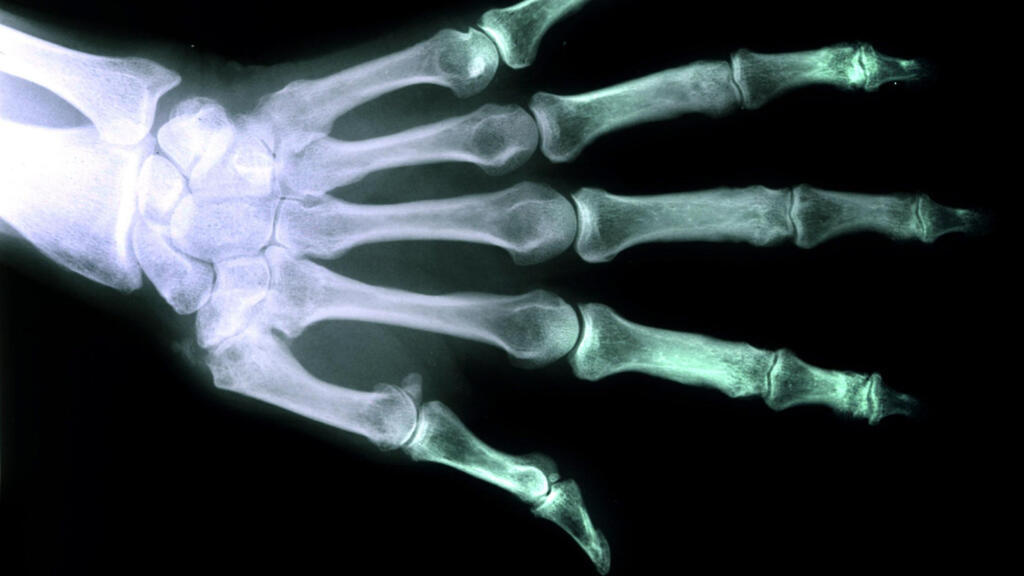

Si la recherche médicale peine encore à générer par impression 3D, un organe humain complet, la jeune pousse Particle3D danoise a mis au point une technique permettant déjà de réaliser sur mesure, des parties entières de notre squelette.

Habituellement, un implant classique est constitué de polymères ou des métaux comme le titane pour créer les os artificiels. Mais le fondateur de la société danoise qui avait rencontré des problèmes de rejets avec ses prothèses métalliques a imaginé de les produire autrement. Son encre biocompatible pour imprimante 3D est à base de particules poudreuses de calcium et de phosphate associés à des acides gras.

Cette matière déjà employée en chirurgie reconstructive nécessitait de sculpter à la main la forme précise du futur implant. Particle3D a automatisé le procédé. Tout commence par un scanner de la zone du corps où sera implanté l’os, ensuite un logiciel analyse la forme précise de l’implant, et l’imprime en 3D avant son envoi au bloc opératoire.

Cette prothèse a l’avantage d’avoir une structure poreuse, et c’est ce qui représente tout l’intérêt de la méthode. Les vaisseaux sanguins et les parties osseuses colonisent ce substrat artificiel pour se reconstituer naturellement au fil du temps. La prothèse finira par se dissoudre, laissant place aux os biologiques. Ce processus réduit le risque de douleurs chroniques et d’infections tout en évitant au patient de nouvelles interventions obligatoires comme c’est le cas actuellement pour retirer les broches et les prothèses classiques. Cette innovation séduit autant les Terriens que les futurs explorateurs de la planète Mars.